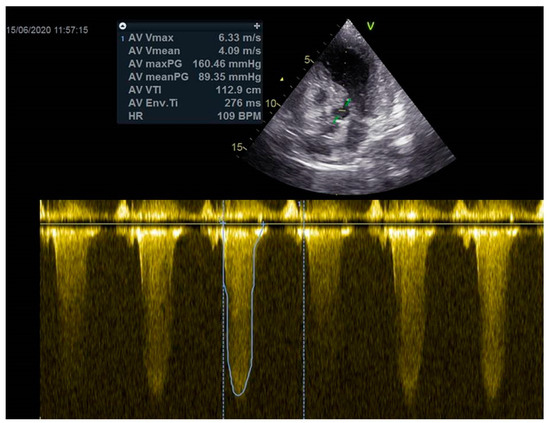

As a result, the patient was referred to a specialized medical institution. Upon admission, the patient was conscious, confused, hypotensive (TA 80/50 mmHg), with a heart rate of about 110/min, and showing clinical signs of hypoperfusion and cardiogenic shock, Killip IV. The medical staff administered sedation, inserted an endotracheal tube, and placed her on invasive mechanical ventilation. The patient was given crystalline solutions, inotrope, and vasopressor medication. An urgent echocardiographic examination was performed due to a rough systolic murmur over the precordium. It revealed akinesia of all medioapical segments of the left ventricle and akinesia basally inferior, where the myocardium was fibrously altered. Other hyperkinetic basal segments formed a dynamic obstruction of the left ventricular outflow tract (LVOTO) with turbulent flow and moderate mitral regurgitation (Figure 2 and Figure 3). The maximum gradient above the LVOT was 160 mmHg (Figure 4). The aortic valve area was 1.8 cm2 (Figure 5). The ejection fraction of the left ventricle (LVEF) was estimated to be 25%. The examination also revealed pericardial effusion with separation between pericardial layers along the right ventricle and atrium of up to 1.2 cm, but without any signs of tamponade.

Figure 4.

The maximum gradient above the LVOT was 160 mmHg.